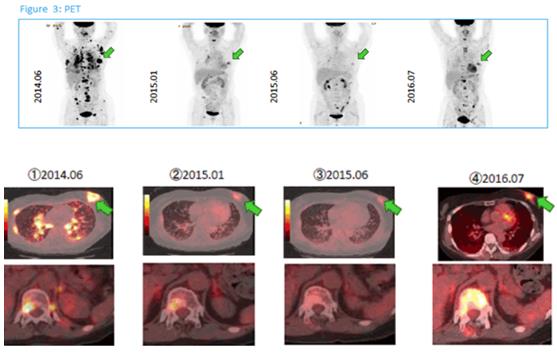

免疫治疗:肺腺癌,男,72岁

稳定状态:病情稳定,在一段时间内肿瘤组织既没有增大也没有缩小。背景介绍 -INTRODUCTION-在日... -